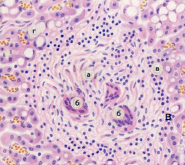

Який морфологічний компонент відрізняє зрілу туберкульому від молодої (незрілої)?

Рис. 1. Гістозріз легень, будова молодої (праворуч) та зрілої (ліворуч) туберкульоми